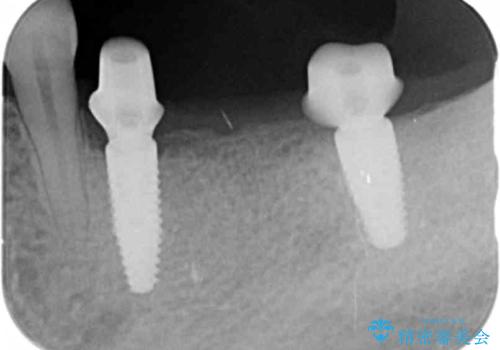

左下の欠損部には強度・表面性状に優れるストローマン社製インプラントを埋入し、合わせて噛み合う上顎の歯もクラウン再補綴による整備を行い安定した咬合関係の構築を目指します。

- 122.1万円(仮歯×5・ストローマンインプラント×2・アバットメント×2・ジルコニアクラウン×5・ゴールドインレー)費用は治療当時の料金となります

歯を失った期間が長くなると、対合する歯が伸びてくることによる補綴スペースの狭小化がしばしば見られます。

今回左下にインプラント治療を行うにあたり、対合する上顎の歯もいっしょに治療を行ったことで安定した咬合関係を構築することができました。